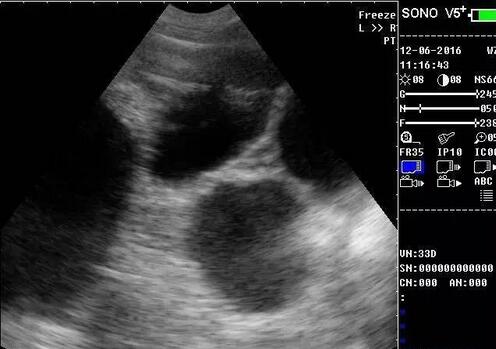

33天怀孕检测图(1/7)